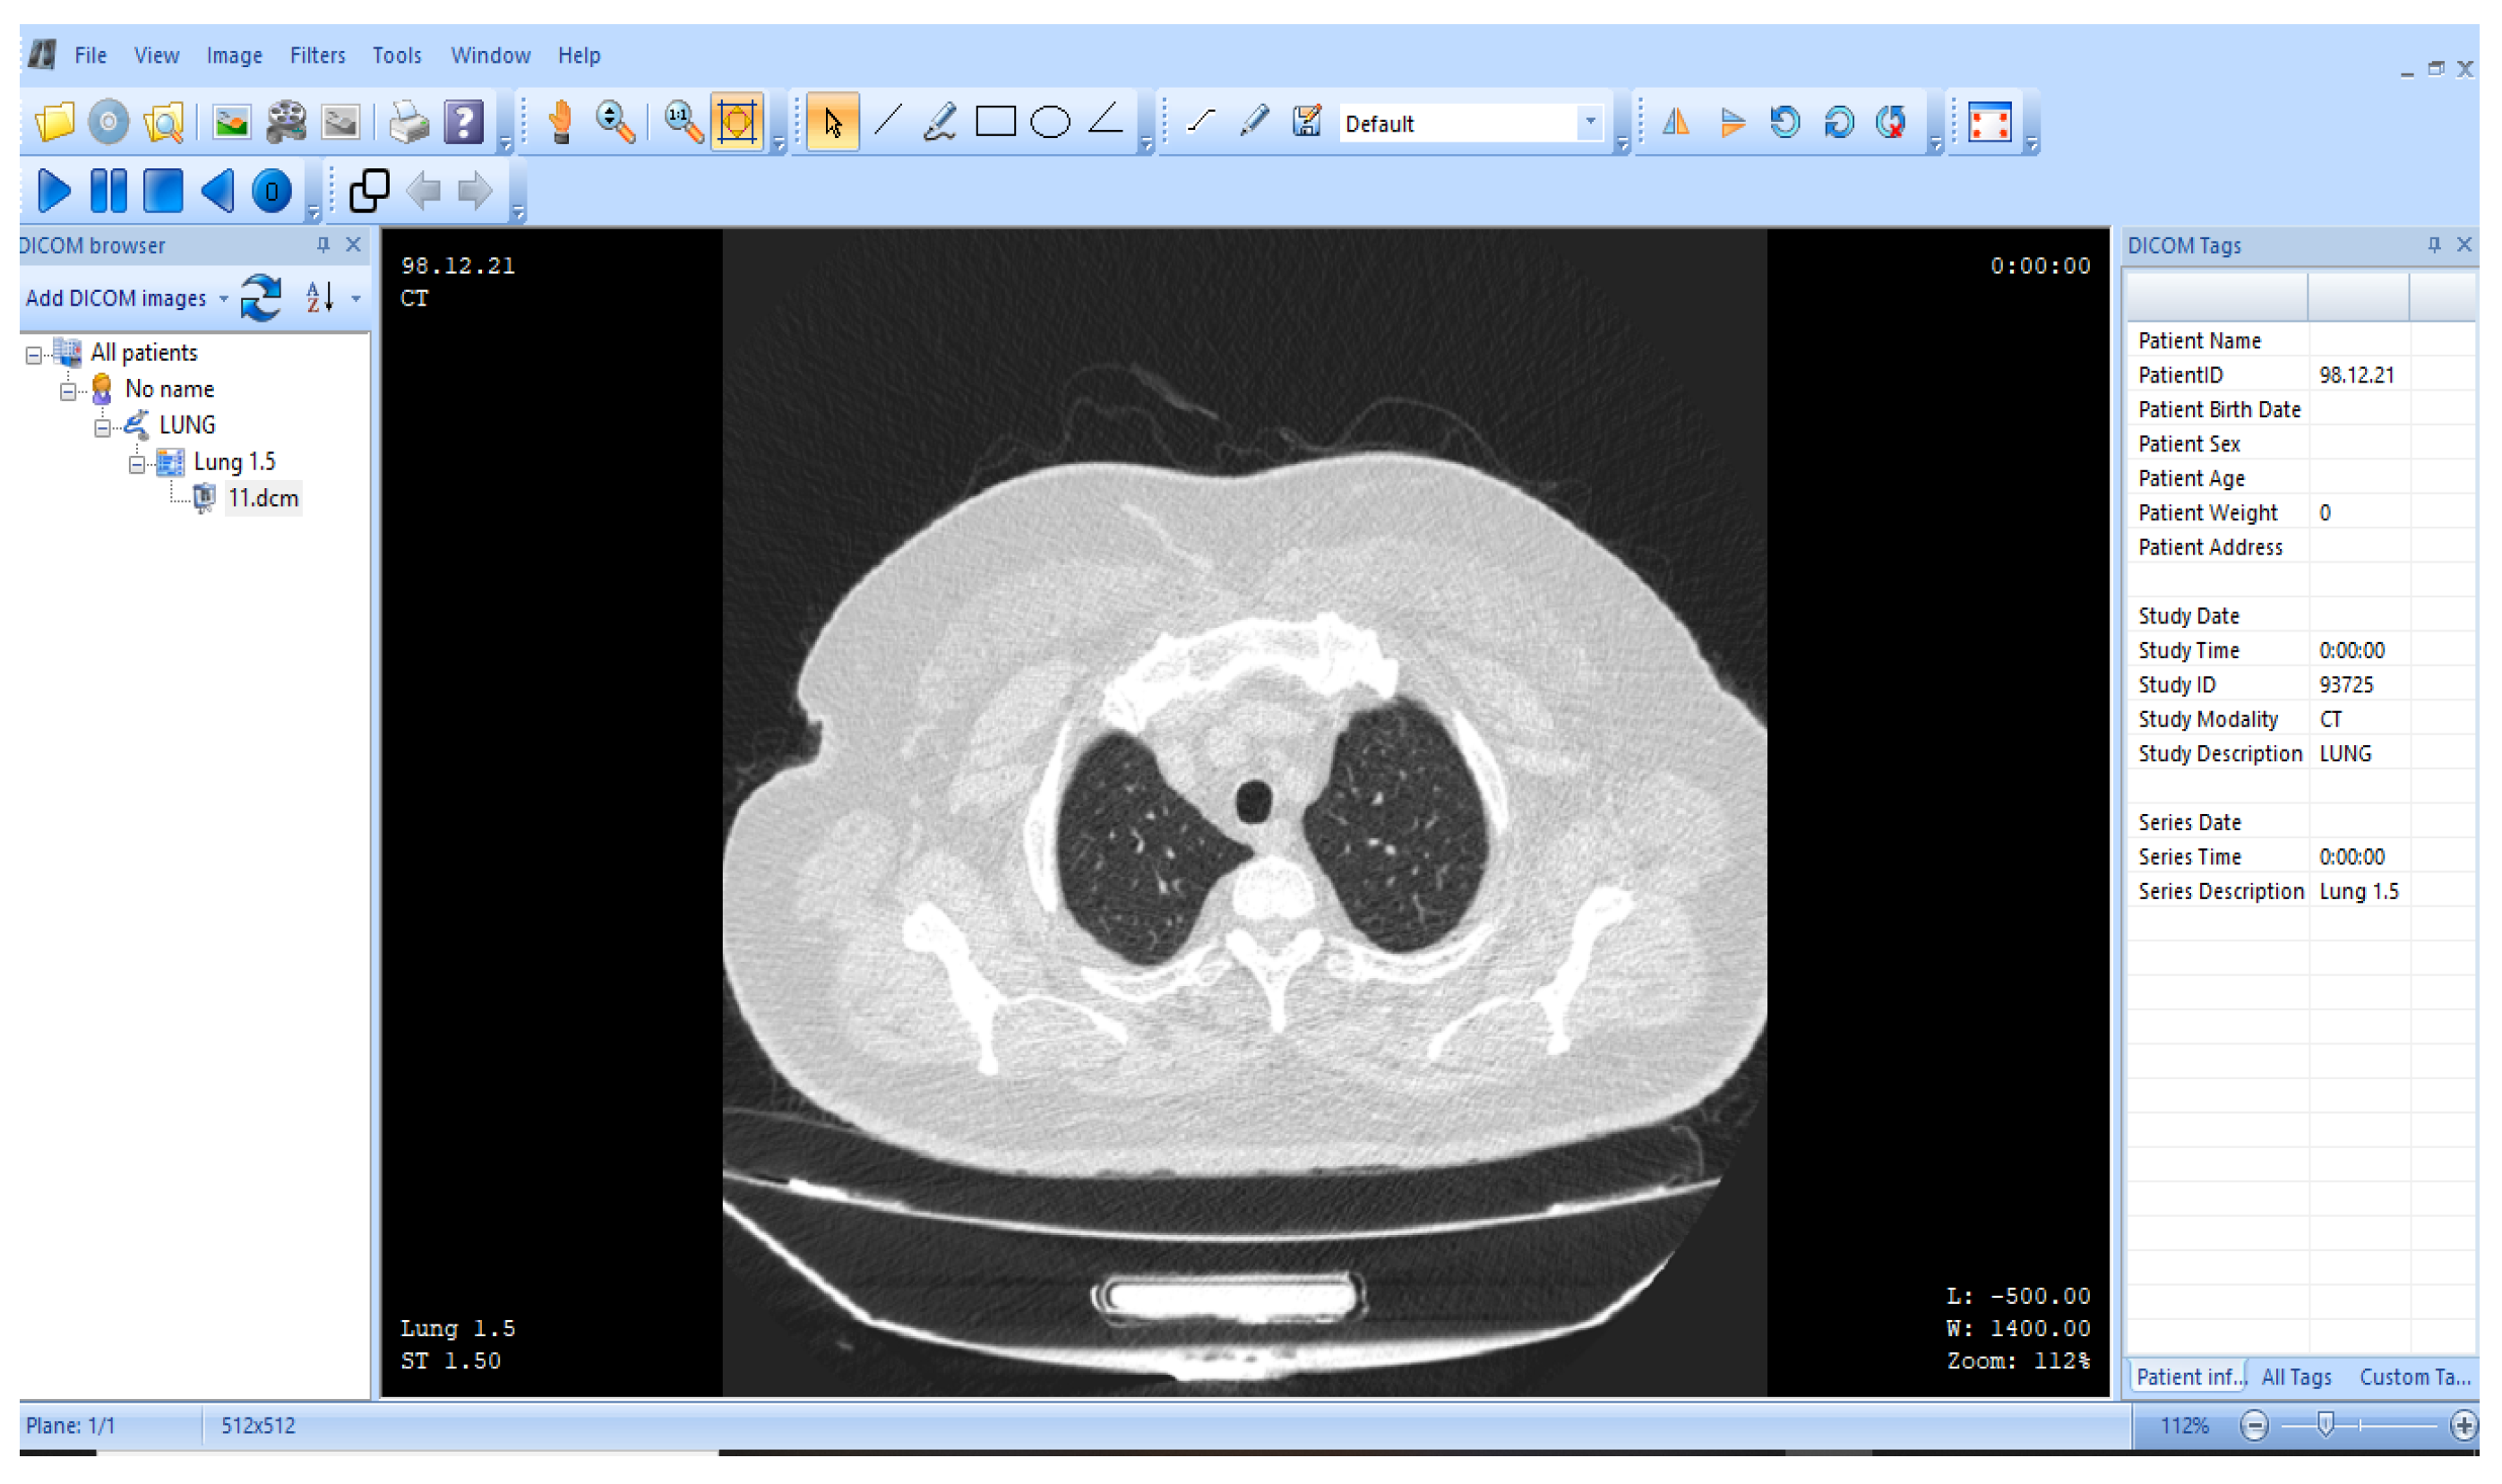

3.1. ROI and NROI-Based Compression of the DICOM Image